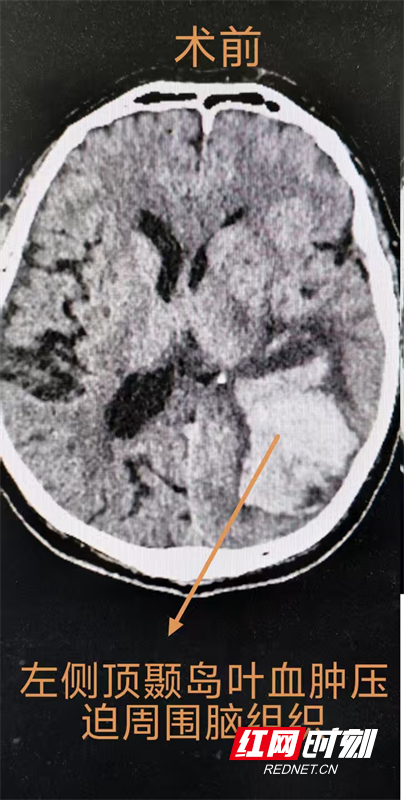

62岁的唐先生因胸闷、胸痛半年,加重1小时入院郴州市第四人民医院心血管内科,被确诊为急性心肌梗死。团队实施急诊冠状动脉造影(CAG)+经皮冠状动脉介入治疗(PIC),暂时稳定了患者的心血管状况。然而术后第一天,患者血小板计数骤降至10×10⁹/L,神志由清醒转为模糊,头部CT检查提示左侧顶叶脑出血,“心脑同病”的复杂情况让治疗更加棘手。

神经外科等科室医生迅速参与会诊,结合患者心脏支架植入后的身体状况,评估认为当前外科手术风险极高,团队一致决定暂时采取保守治疗,将患者转入NICU进行24小时严密监护。由于患者接受了心脏支架手术,需服用抗凝药物防止支架内血栓形成,而抗凝药物又可能导致脑出血继续增加,手术后新发出血可能性很高,主动耐心细致地与患者家属沟通病情及治疗方案,打消他们的顾虑。4天后患者左侧脑内出血量明显增加,可能危及生命,随即启动多学科协作讨论,联合心血管内科、ICU、麻醉科评估手术风险及耐受性,决定采用颅骨钻孔血肿碎吸引流术这一微创术式,精准定位、颅骨钻孔、血肿腔穿刺引流,短短数十分钟,手术取得圆满成功。